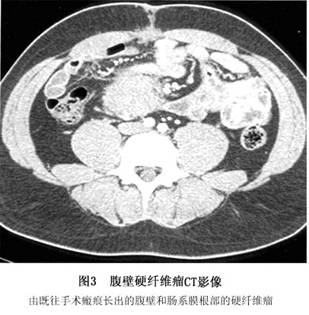

2.CT扫描 硬纤维瘤在CT上大部分呈边界清楚、密度均匀的软组织肿块。但病变小时往往边界不清晰,病变大时一组肌肉已被肿瘤“蚕食”,周围有皮下脂肪相衬,多显示边界比较清晰。肿瘤平扫呈均匀等密度。增强扫描较平扫能更好显示肿瘤边界,边界极不规则,呈浸润状,肿瘤呈爪样蚕食正常肌肉(图3)。

增强扫描时与肌肉比较:肿瘤较大时,病灶密度略高或等肌肉密度中有小梁状、条状或呈偏心的较大圆形低密度改变分散其间,小梁状或条状与原肌纤维走向一致;如果肿瘤较小,组织学显示肿瘤组织间仍有一定量的正常肌肉组织,但不足以在影像上表现出来,因而CT扫描呈均匀等密度或略高密度。亦有极少文献报道硬纤维瘤可见钙化、软骨化或骨化。但有学者认为,腹壁硬纤维瘤多较小,平扫与增强多呈均匀的等密度,仅表现局部肌肉略肿胀,脂肪间隙模糊;因腹壁肌群少而薄,爪样浸润及肿瘤中偏心的多个低密度改变这两个特征的征象常常不能表现出来,须结合临床考虑。